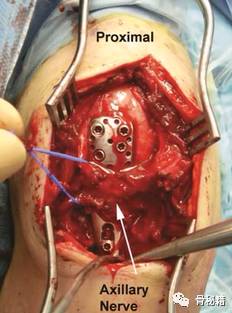

该入路需要注意几个问题

1、需要注意入路时,从三角肌的前、中肌肉之间进入

2、注意分辨关节囊

3、需要注意腋神经!

该腋神经横跨肱骨干,需要小心分离保护,不能过度牵拉

然后就可以进入肱骨近端了,整体暴露图 上方为小结节,下方为大结节。